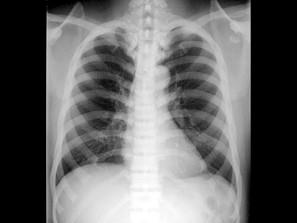

男,23岁,根据影像图像,最可能的诊断是?(?)A.骨髓炎B.骨硬化症C.骨囊肿D.骨脓肿E.骨结核

问题 男,23岁,根据影像图像,最可能的诊断是?(?)

选项 A.骨髓炎 B.骨硬化症 C.骨囊肿 D.骨脓肿 E.骨结核

答案 B